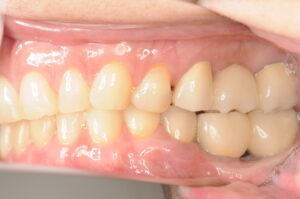

口腔内所見

レントゲン写真で確認すると、欠損期間が長いために歯槽骨の吸収が進行しており、インプラントをそのまま埋入するには骨量が不足していました。特に第一大臼歯部はブリッジの影響もあり、骨の幅が薄くなっていました。

このため、骨造成(GBR)を併用して十分な骨量を確保する必要があると診断しました。